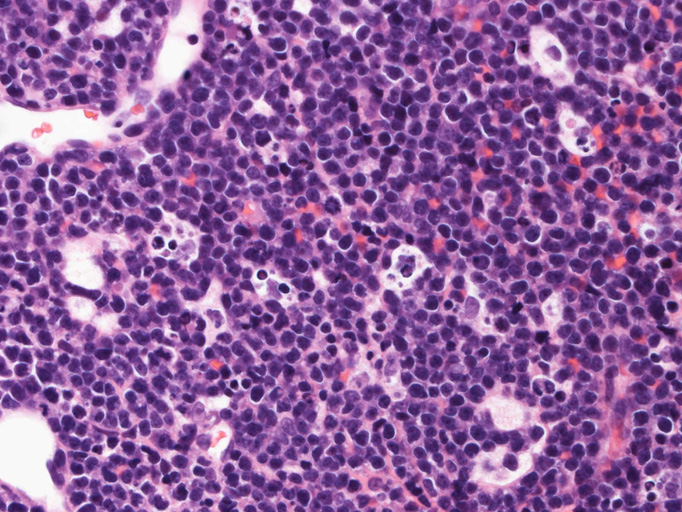

Burkitt lymphoma

Burkitt's lymphoma--症例01

組織・細胞病理所見

エコーガイド下肝腫瘤針生検組織

尾状葉の腫瘍から16G, 11mm穿刺針で5mm, 2mmの組織を採取した。2mmの組織は線維組織と肝組織で腫瘍細胞を含んでいなかった。穿刺針洗浄液をkaryotypeに提出する。